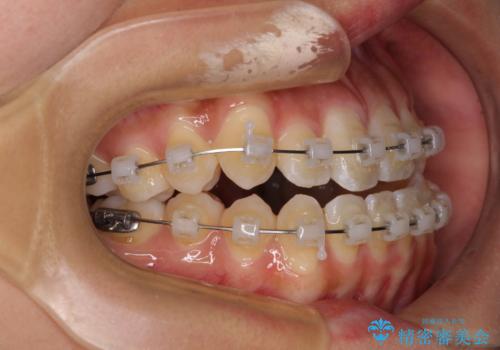

- クリアブラケット

- 1年6ヶ月

- 10-30回

急速拡大装置で上顎骨を十分に拡大できたことで、非抜歯で八重歯を歯列に納めることができました。

患者様はもちろん、我々もここまで綺麗に仕上げられるとは想像もできず、お互いに大変満足な治療となりました。